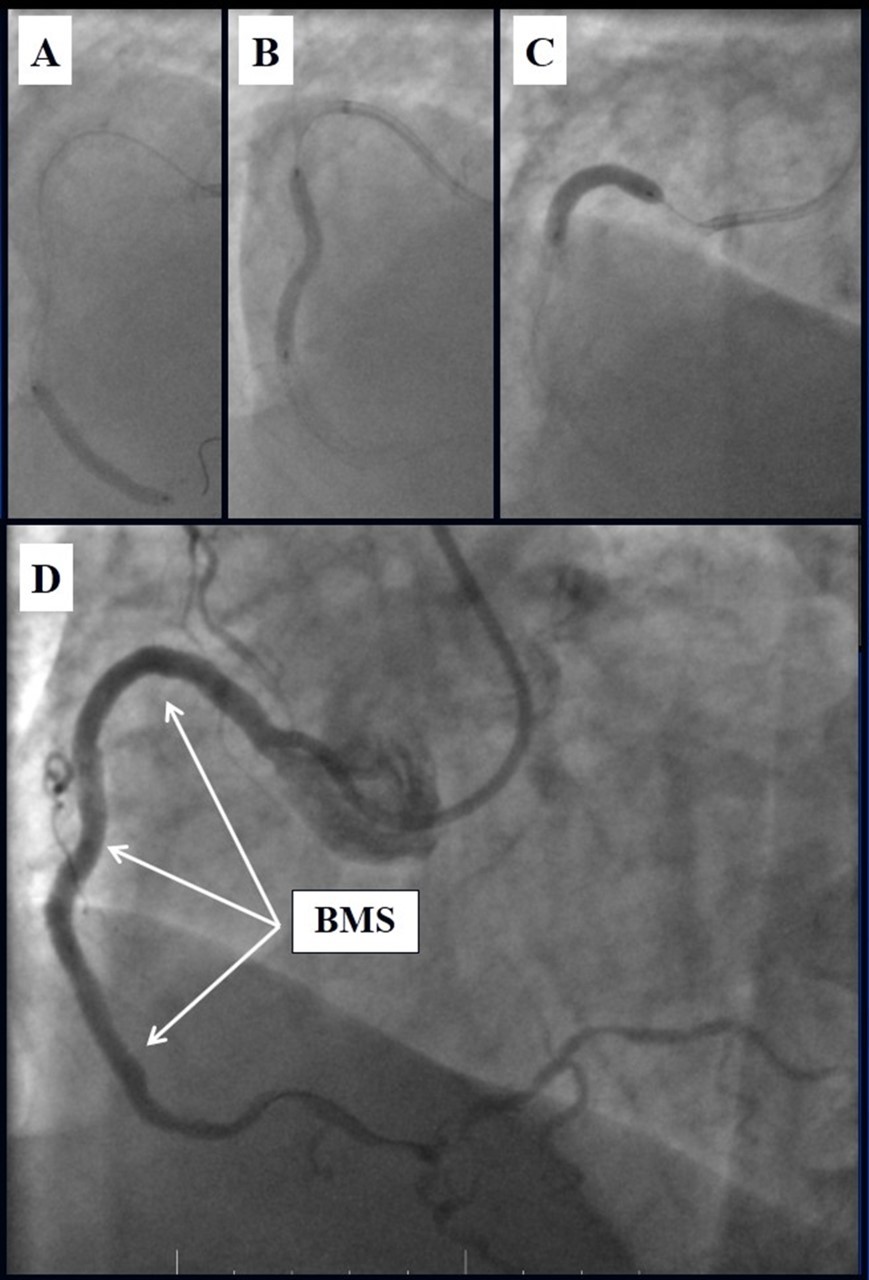

In the first stage, despite the fact that BMS is contraindicated in diabetic patients, RCA was stented with 3 bare-metal stents (BMS) (Rebel, Boston Scientific) (due to financial problems - drug-eluting stents was not covered by insurance). We used BMS to have at least temporarily patent RCA during LMCA stenting (Figure 5) (we believe that, when RCA is functional, LMCA stenting is safer). LAD was stented with 2 drug-eluting stents (Resolute Integrity, Medtronic). After the first PCI patient’s symptoms were relieved (Figure 6).

Figure 5.A, B, C - Stenting of the RCA with BMS; D - Angiography result.